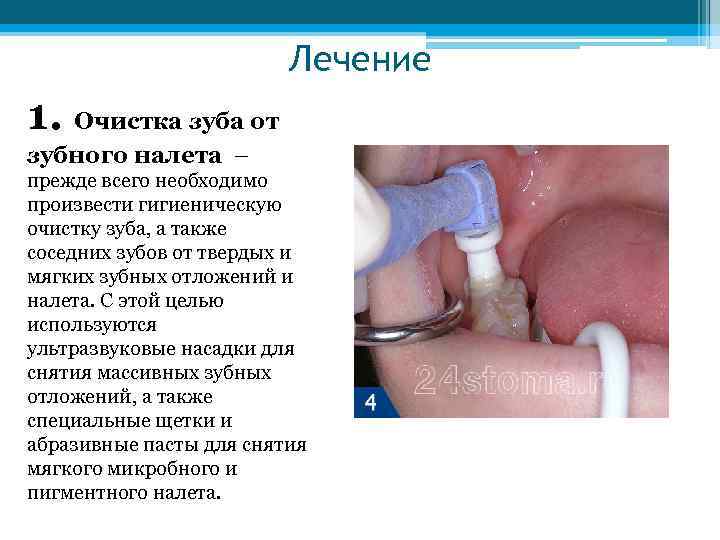

Лечение 1. Очистка зуба от зубного налета – прежде всего необходимо произвести гигиеническую очистку зуба, а также соседних зубов от твердых и мягких зубных отложений и налета. С этой целью используются ультразвуковые насадки для снятия массивных зубных отложений, а также специальные щетки и абразивные пасты для снятия мягкого микробного и пигментного налета.

Лечение 1. Очистка зуба от зубного налета – прежде всего необходимо произвести гигиеническую очистку зуба, а также соседних зубов от твердых и мягких зубных отложений и налета. С этой целью используются ультразвуковые насадки для снятия массивных зубных отложений, а также специальные щетки и абразивные пасты для снятия мягкого микробного и пигментного налета.